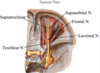

Branches of the frontal nerve and their function:

- Trigeminal

- Ophthalmic (V1)

- Frontal

- Supraorbital

- Supratrochlear

SENSORY TO SKIN OVER ORBIT AND FOREHEAD

Label all: